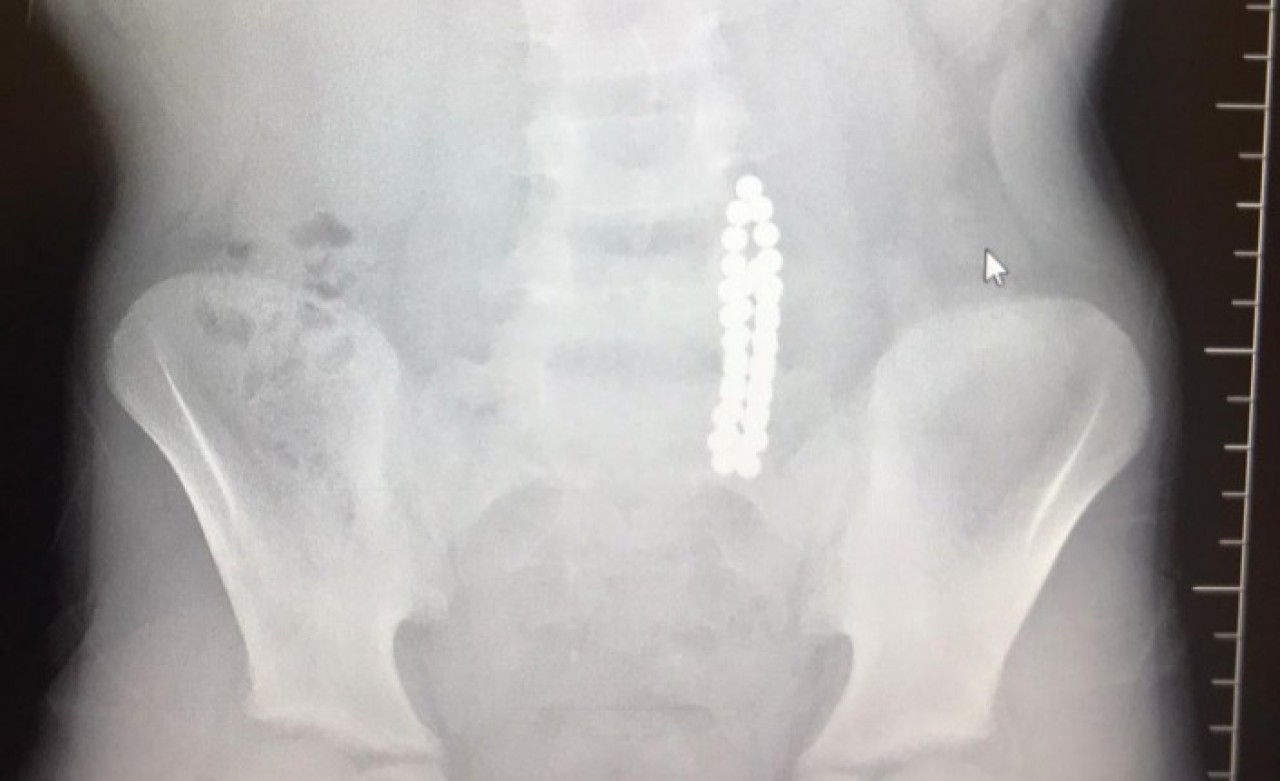

İstanbul Beylikdüzü'nde 9 yaşındaki bir çocuk ailesinin haberi olmadan neodyum adı verilen stres bilyeleri olarak da bilinen 42 adet mıknatısı yuttu. Birkaç gün sonra şiddetli karın ağrısı ve kusma şikayeti ile hastaneye gelen çocuğun röntgeni çekildi.

Röntgen filminde çocuğun midesinde boncuklar halinde yabancı bir cisim tespit edildi. Bağırsağını delen cismi fark eden Beykent Üniversitesi Çocuk Cerrahisi Uzmanı Prof. Dr. Ali Çay çocuğu ameliyata aldı. Yapılan ameliyatta çocuğun bağırsaklarından rengarenk şekilde 42 adet neodyum çıkarıldı.

Konuyla ilgili konuşan Prof. Dr. Çay, yutulan cisimlerin normalde sindirim sistemi ile çıkabileceğini ancak çoklu mıknatısların bağırsaklarda delinmeye neden olabileceğini ifade ederek, "Bizim hastamız yaklaşık 42 tane bu mıknatıstan yutmuş çeşitli hastanelere müracaat etmiş. Burada yapılan incelemelerde çekilen filmlerde tesadüfen bu mıknatısları yuttuğunu biz radyografide gördük hastamızı ameliyata aldık. İnce bağırsak uç kısmında delinme oluşturmuştu. Biz bu mıknatısları çıkardık" dedi.